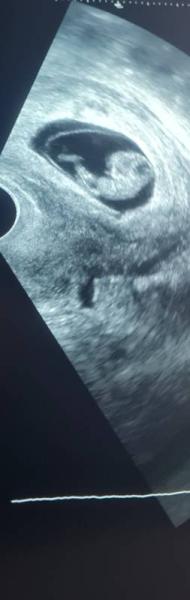

Ich stelle mich mal vor: Ich bin 25 Jahre alt, mein Partner ist 27 und wir sind seit 6 Jahren ein Paar. Geplant war die Schwangerschaft erst ab nächstes Frühjahr, der Krümel hatte es jedoch ein wenig eiliger Das Herzchen wummert ganz freudig und gewunken hat es beim Ultraschall auch schon fleißig. :) ET wurde bis jetzt auf den 12.07.21 festgelegt. Nächste Woche mach ich den Harmony Test, obwohl es dafür eigentlich keinen Grund gibt.... mein Freund ist sehr ängstlich und will das unbedingt. Zu uns gehört noch eine 1 1/2 jährige Hündin, die mir seit der Schwangerschaft nicht mehr von der Seite weicht und wann immer es geht mit meinem Bauch kuschelt. Seit der 6Ssw bin ich im Beschäftigungsverbot, da ich in einem Heim für auffällige Kinder arbeite. Dank Corona ist die Langeweile doch sehr groß tagsüber.. Ich freue mich über einen regen Austausch hier :)

Sollst du dann bis zum Mutterschutz digitalen Unterricht machen oder wie wird das bei dir geregelt? Schwangerschaftssymptome habe ich seit 4 Wochen extreme Übelkeit, zum Glück nur 1x erbrochen. Dadurch habe ich auch knapp 2kg abgenommen, weil ich an manchen Tagen nur Zwieback essen konnte. Müdigkeit tagsüber auch stark, dafür kann ich dann abends im Bett nur schlecht einschlafen. Wie ist es da bei dir mit Symptomen? Mein Partner durfte leider auch nicht mit zum Ultraschall Termin, dafür durfte ich mit dem Handy das zappelnde Böhnchen filmen, das hat es etwas entschädigt und man hat nicht nur ein Foto zur Hand. :) Ja, ab der 14. SSW bekommen wir dann auch das Geschlecht gesagt. Darauf freuen wir uns schon, da das keine Spekulation zulässt. Hast du schon nach Hebammen Ausschau gehalten? Meine FA hat mir dazu geraten, mich bald auf die Suche zu machen. Finde das nur so surreal, das jetzt schon zu tun. Lg